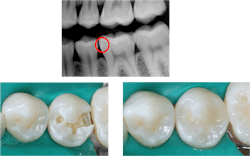

Historically, with a few exceptions, crowns did not come off in service. Zinc phosphate and conventional GI cements are rigid and strong and held the crowns on the tooth preparations. Resin cements are flexible and strong (figure 3). But one of the major reasons almost every dentist has had zirconia crowns coming off is the flexibility of resin cements and, to a lesser degree, the flexibility of the RMGI cements (figure 4).

Dentists need rigid, strong, cariostatic cements almost every day of practice. As with composite restorative materials, resin cements need cariostatic properties immediately! In the interim, until resin cements are modified, I suggest that dentists should use RMGI and GI cements for crowns and fixed prostheses.

Dental root-form titanium alloy implants were originally thought to replace teeth ideally, and even potentially to be better than teeth. Decades later, we know that is not true. Peri-implantitis, occlusal challenges, and numerous other issues have shown us that our main mission is still preservation and retention of natural teeth and that implants are a great “last resort” when teeth cannot be restored and retained (figure 4).